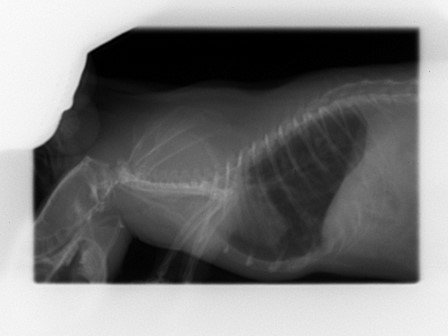

Découverte de multiples foyers infectieux dans les poumons :

Par radio, en janvier 2022.

A ce stade le véto n'est pas inquiet, car bien que multiples les tâches sont très infimes et les poumons restent intègres ; il me recommande de la surveiller de très près et me prévient que si une décompensation doit se faire se sera surement silencieusement (donc surveillance du poids et du mouvement respiratoire).

Le 25 mai je fais faire les radios de contrôle car je la trouve un chouya plus fine des flancs et on observe que l'aspect des foyers infectieux est plus "moucheté" ; c'est pas la cata encore (poumons toujours intègres) mais comme y'a tout de même évolution on commence le traitement : Doxy pour au moins deux semaines.

Voilà les radios ; pour chaque ligne :

• à gauche = janvier

• à droite = mai

KISS 2022 01 03 (1).jpgKISS 2022 05 25 (2).jpg

KISS 2022 01 03 (2).jpgKISS 2022 05 25 (1).jpg

• La radio montre que son cœur est légèrement décollé de l'endroit où il devrait être, mais sans que ça soit un soucis.